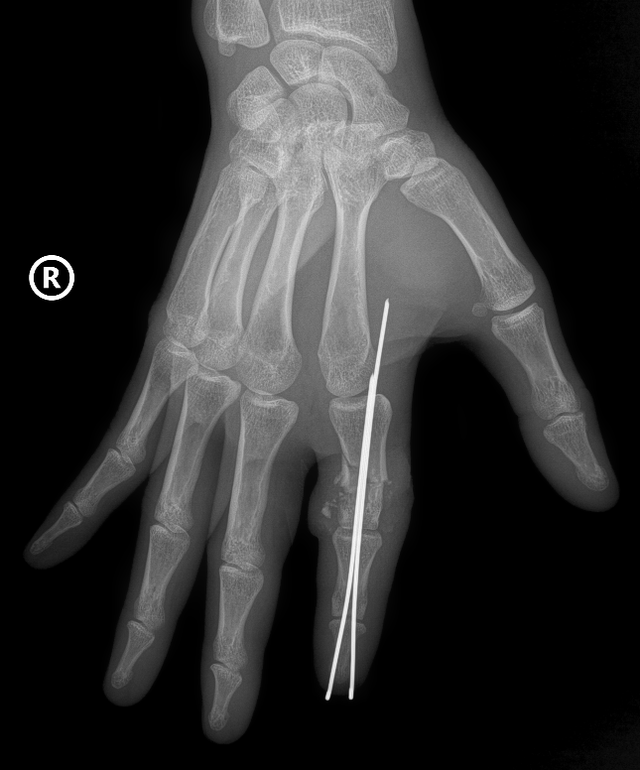

Ca mổ được tiến hành khẩn cấp. Ê-kíp phẫu thuật đã vi phẫu nối lại toàn bộ cấu trúc vi thể gồm động mạch, tĩnh mạch, thần kinh, gân gấp, gân duỗi và cố định xương. Do ngón tay thiếu máu lâu, việc tái lập dòng chảy là thách thức lớn nhất.

Mạch và thần kinh ngón tay anh D. được phục hồi

Sau nhiều giờ phẫu thuật, tuần hoàn ngón tay đã được khôi phục. Sau mổ, ngón tay hồng ấm trở lại – dấu hiệu cho thấy mô đang phục hồi tốt. Hiện sức khỏe anh D. ổn định, ngón tay được theo dõi tưới máu liên tục và diễn tiến khả quan.

Sau phẫu thuật, vết thương của bệnh nhân đã liền, ngón tay hồng, sống hoàn toàn, người bệnh đã có thể cắt chỉ và rút kim cố định. Hiện, bệnh nhân đang được tập phục hồi chức năng để lấy lại khả năng vận động và cảm giác của ngón tay.

Sau phẫu thuật, vết thương của bệnh nhân đã liền, ngón tay hồng, sống hoàn toàn, người bệnh đã có thể cắt chỉ và rút kim cố định.